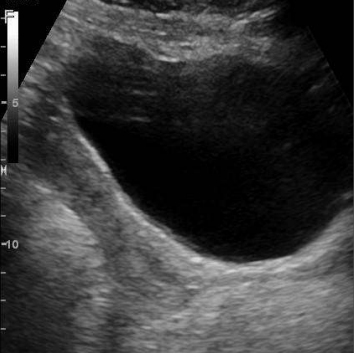

<p>Artefacto más evidente en este quiste</p>

Artefacto más evidente en este quiste

Refuerzo acústico posterior